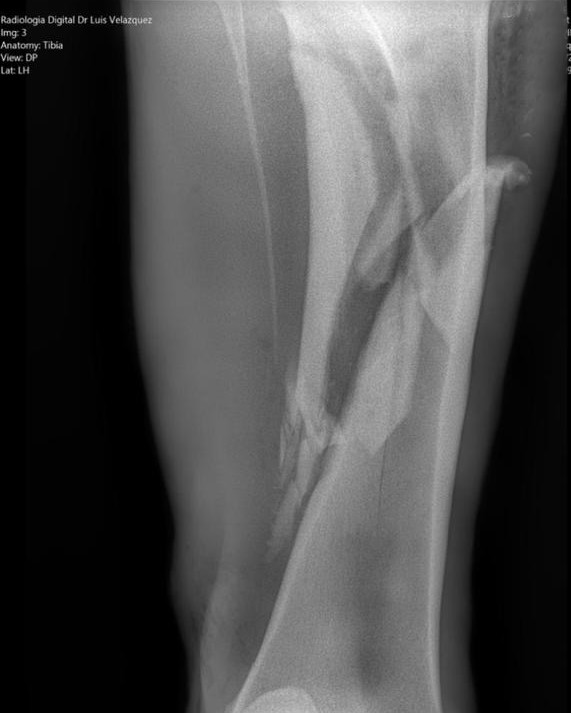

Radiología Digital como Herramienta Complementaria en el Dictamen de Bienes Muebles